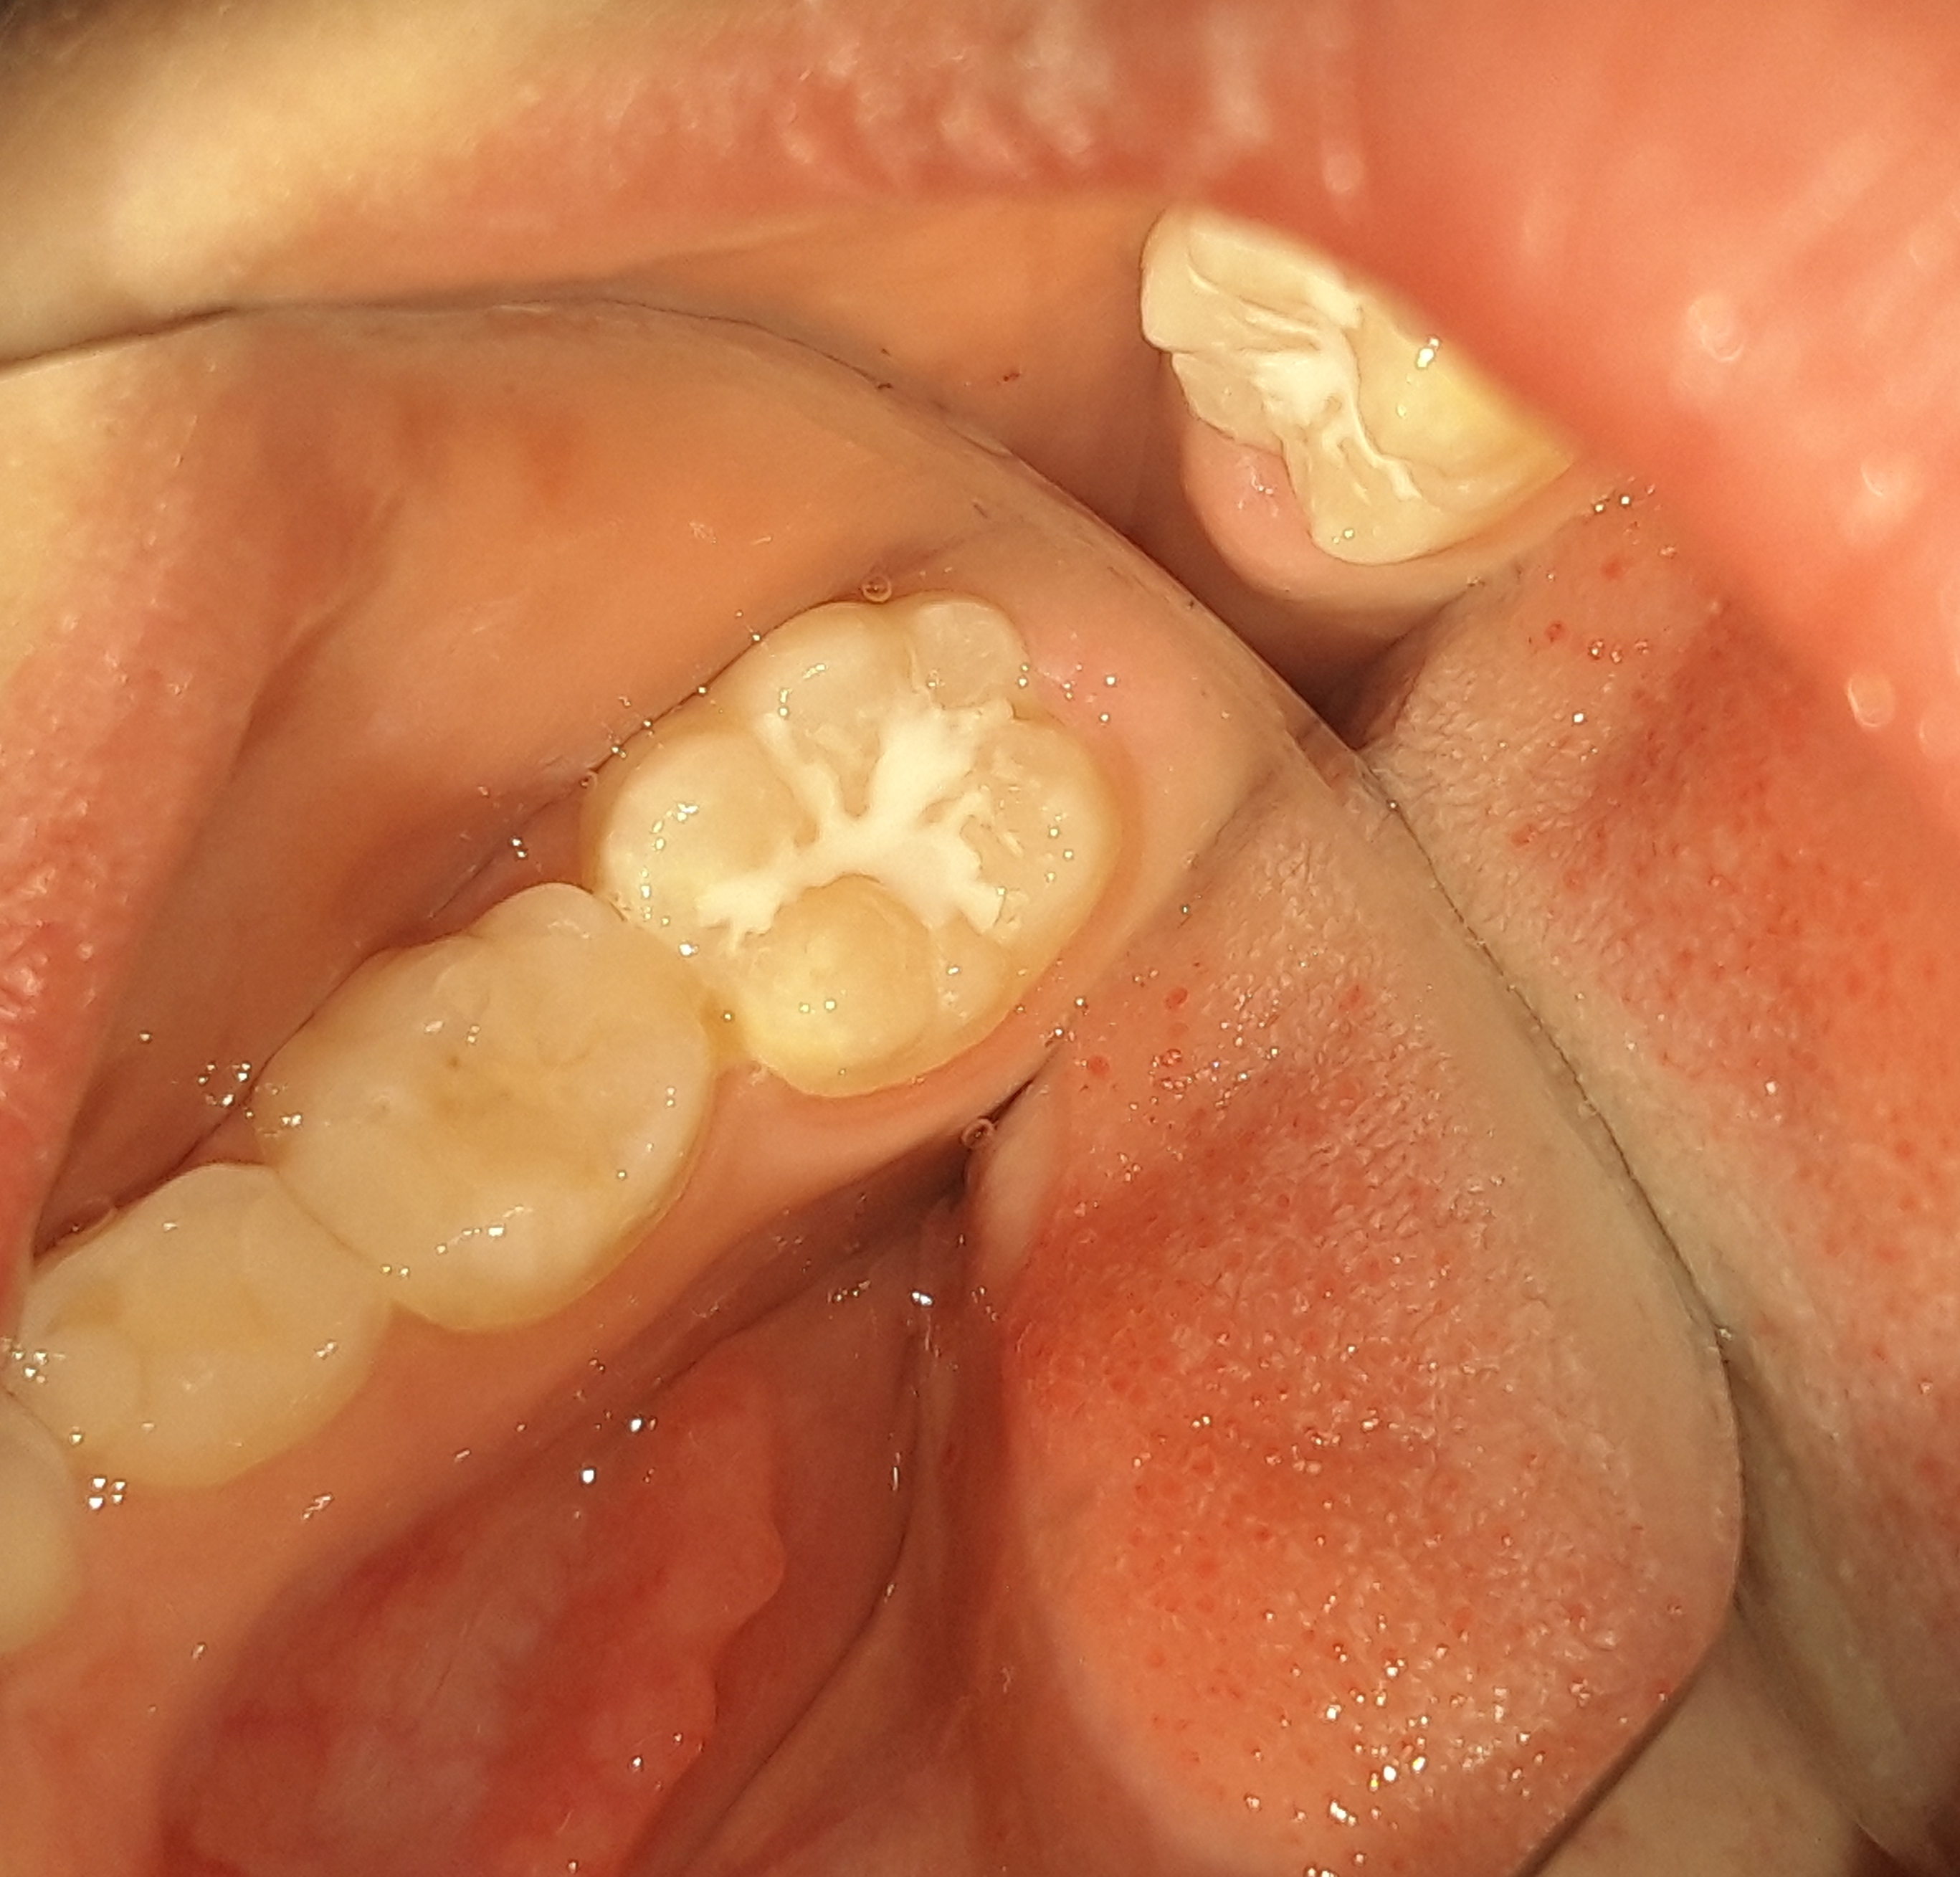

Περιστατικό – Σφραγίσματα νεογιλών δοντιών και sealant / προληπτική κάλυψη οπών και σχισμών

Στο συγκεκριμένο περιστατικό πραγματοποιήθηκαν 2 λευκά σφραγίσματα στα 2 τελευταία οπίσθια νεογιλά και συγχρόνως προληπτική κάλυψη οπών και σχισμών (sealant) στη μασητική επιφάνεια του πρώτου μόνιμου γομφίου. Απουσιάζει η φωτογραφία της αρχικής κατάστασης των δοντιών.